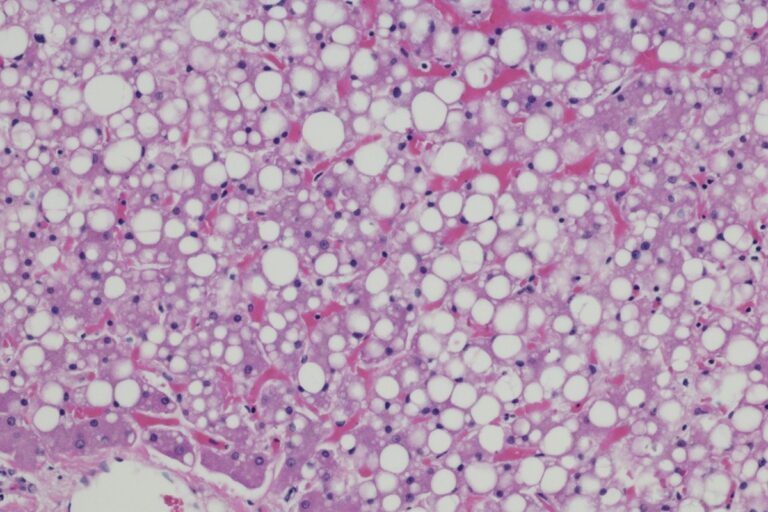

O quadro, que está relacionado à obesidade, sedentarismo e resistência à insulina, é caracterizado pelo acúmulo de células de gordura no tecido do fígado.

“O problema começa de forma discreta, mas pode evoluir para inflamações crônicas e fibrose, aumentando o risco de cirrose e câncer de fígado”, explica o endocrinologista Paulo Bittencourt, presidente do Instituto Brasileiro do Fígado (Ibrafig).